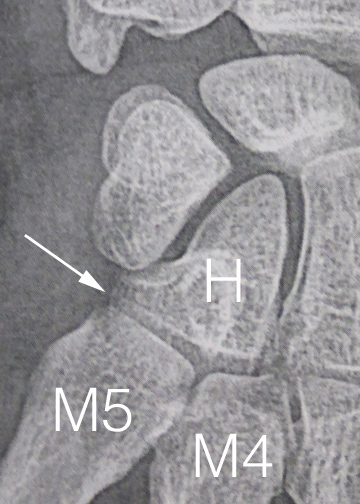

Ces fractures sont difficiles à analyser sur les radiographies et sont souvent à l’origine de séquelles car les surfaces articulaires sont restées déformées par l’accident et aboutissent à de l’arthrose.

Cette technique consiste à créer un espace entre la base du cinquième métacarpien (M5) et l’hamatum (H) tout en conservant la mobilité des deux derniers métacarpiens.